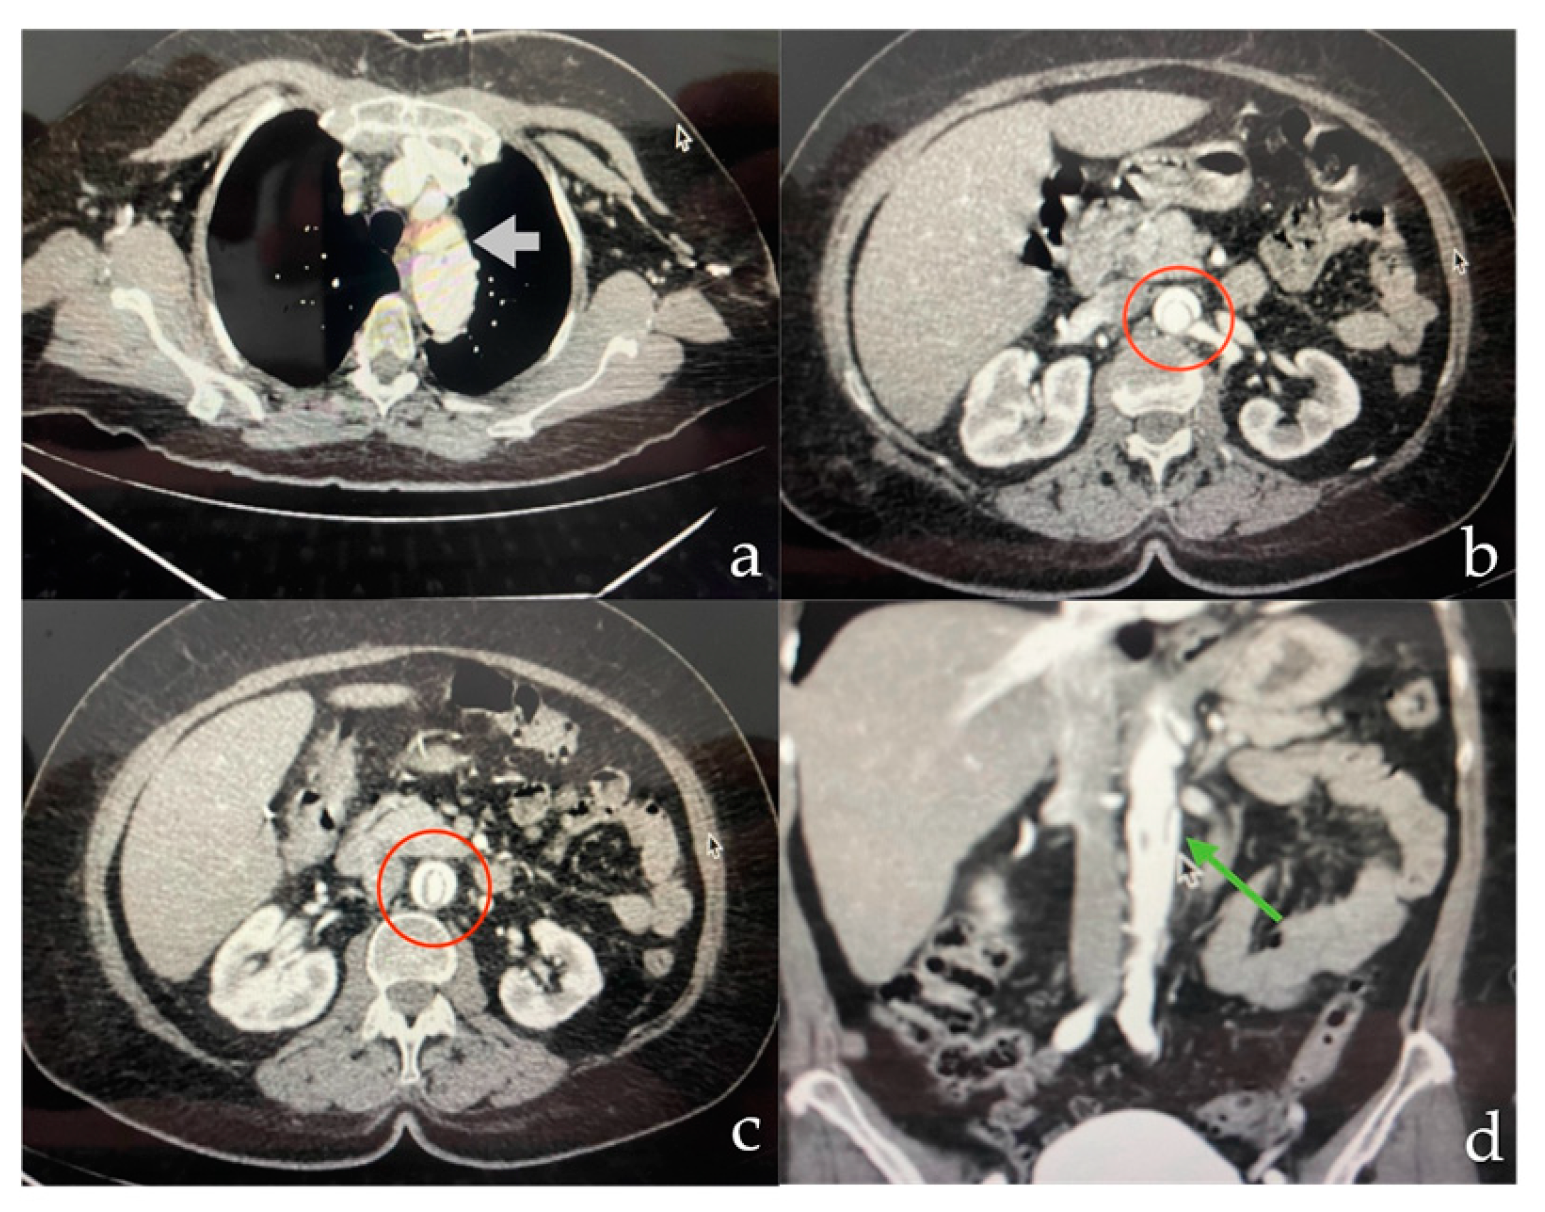

Consequently, the patient was transferred to the operating room for staged hybrid management. It was decided to perform Zone 1 coverage, starting with a cervical debridement procedure that included a carotid-carotid bypass. Access was gained through a retropharyngeal route and space was created for the tunnel by blunt dissection medial to the common carotid artery and retroesophageal. After completing the carotid-carotid bypass, the anterior scalene muscle was divided to access the subclavian artery. A lateral arteriotomy was performed on the left common carotid artery and an end-to-end anastomosis was performed using a 6 mm polytetrafluoroethylene (PTFE) ringed graft (Gore-Tex) with 5/0 prolene sutures (Figure 3). Hemostasis was ensured and revascularization of the left subclavian artery was achieved before removal of the vascular clamp. After the procedure, the patient was transferred to the Intensive Care Unit (ICU).

Figure 3. Cervical debranching (a) Carotid artery bypass (b, c) Bypass of carotid and subclavian artery (d) Cervical Debranching arteriography.